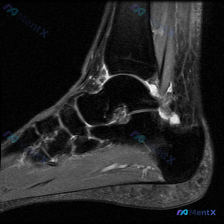

整理了一份足踝MRI读片病例,分享下分析思路,大家可以一起讨论。 病例影像基础信息 这是一张足踝部T2加权矢状位MRI,显示跟骨、距骨、部分跗骨和足底结构: - 骨骼:跟骨和距骨骨髓信号基本正常,皮质边缘清晰,未见明显异常信号 - 关节:跟距关节间隙清晰,无明显关节面侵蚀或严重狭窄 - 异常发现:跟...